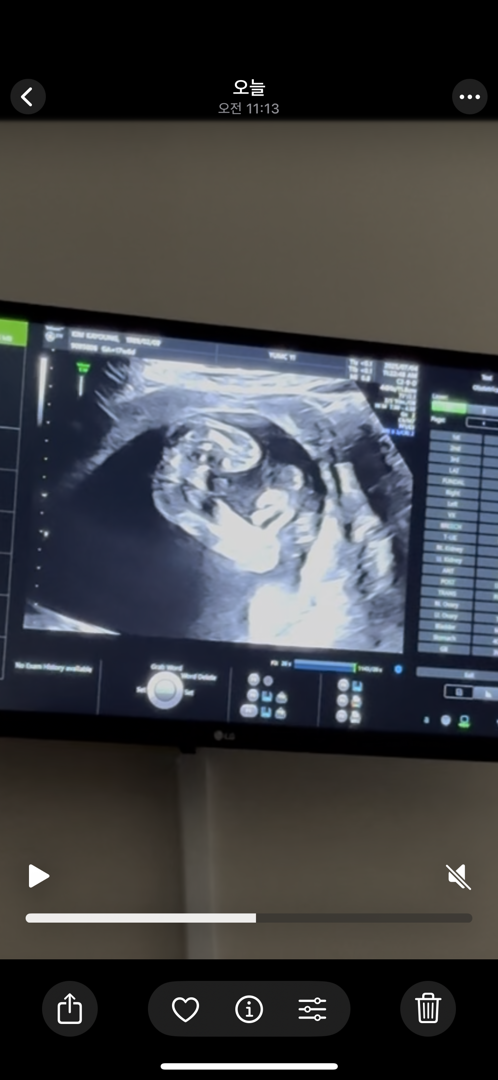

17주 성별 문의

안녕하세요. 쌍둥이맘입니다. 17주에 초음파를 봤는데 둘째 성별이 애매해서 문의드려요. 아들일까요 딸일까요?